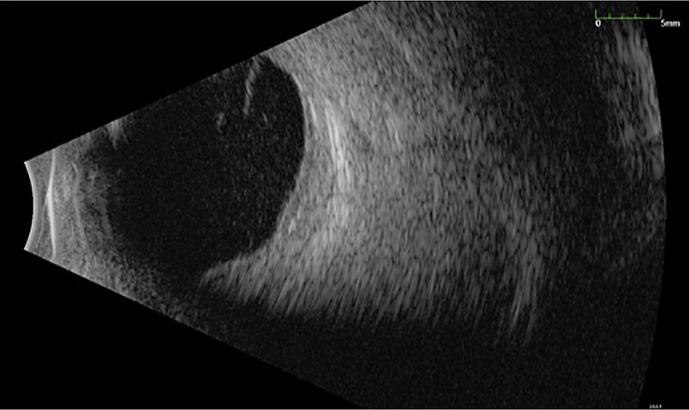

Case presentation: A 76-year-old man with a past medical history of cutaneous melanoma on the right shoulder status post radiation presented to the ocular oncology clinic with a 3-month history of decreased vision, occasional pain, and floaters in the right eye. Initial examination revealed a visual acuity of hand motion in the right eye, intraocular pressure of 5 mm Hg, and no view to the fundus due to vitreous hemorrhage. B-scan did not show a retinal tear, retinal detachment, or intraocular tumor. The patient underwent pars plana vitrectomy of the right eye where massive choroidal thickening with subretinal yellow deposits obstructing the optic nerve head was seen, initially concerning lymphoma. On postoperative week one, visual acuity remained hand motion and the fundus exam showed clear vitreous and retinal/choroidal infiltrates obscuring the optic nerve and macula. Repeat B-scan showed retinal and choroidal thickening with exudates. Cytology results from surgery later revealed malignant cells consistent with melanoma. The patient underwent ocular radiation but eventually progressed to no light perception visual acuity. He is currently under observation with the goal of palliative care.